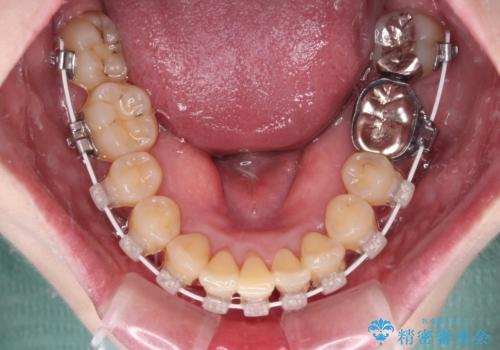

- 矯正装置

- 審美装置

- 八重歯と正中のズレを気にして来院された患者様です。

上顎左側が八重歯になっており、上顎正中が左側にずれていました。

上顎左側の第一小臼歯を抜歯し、補助装置を用いて正中位置を改善しながら八重歯を解消していくこととしました。

下顎前歯が1本欠損していたため、上下正中の位置が合わせるという目標はなく、鼻筋に上顎正中を合わせていくように移動を行いました。